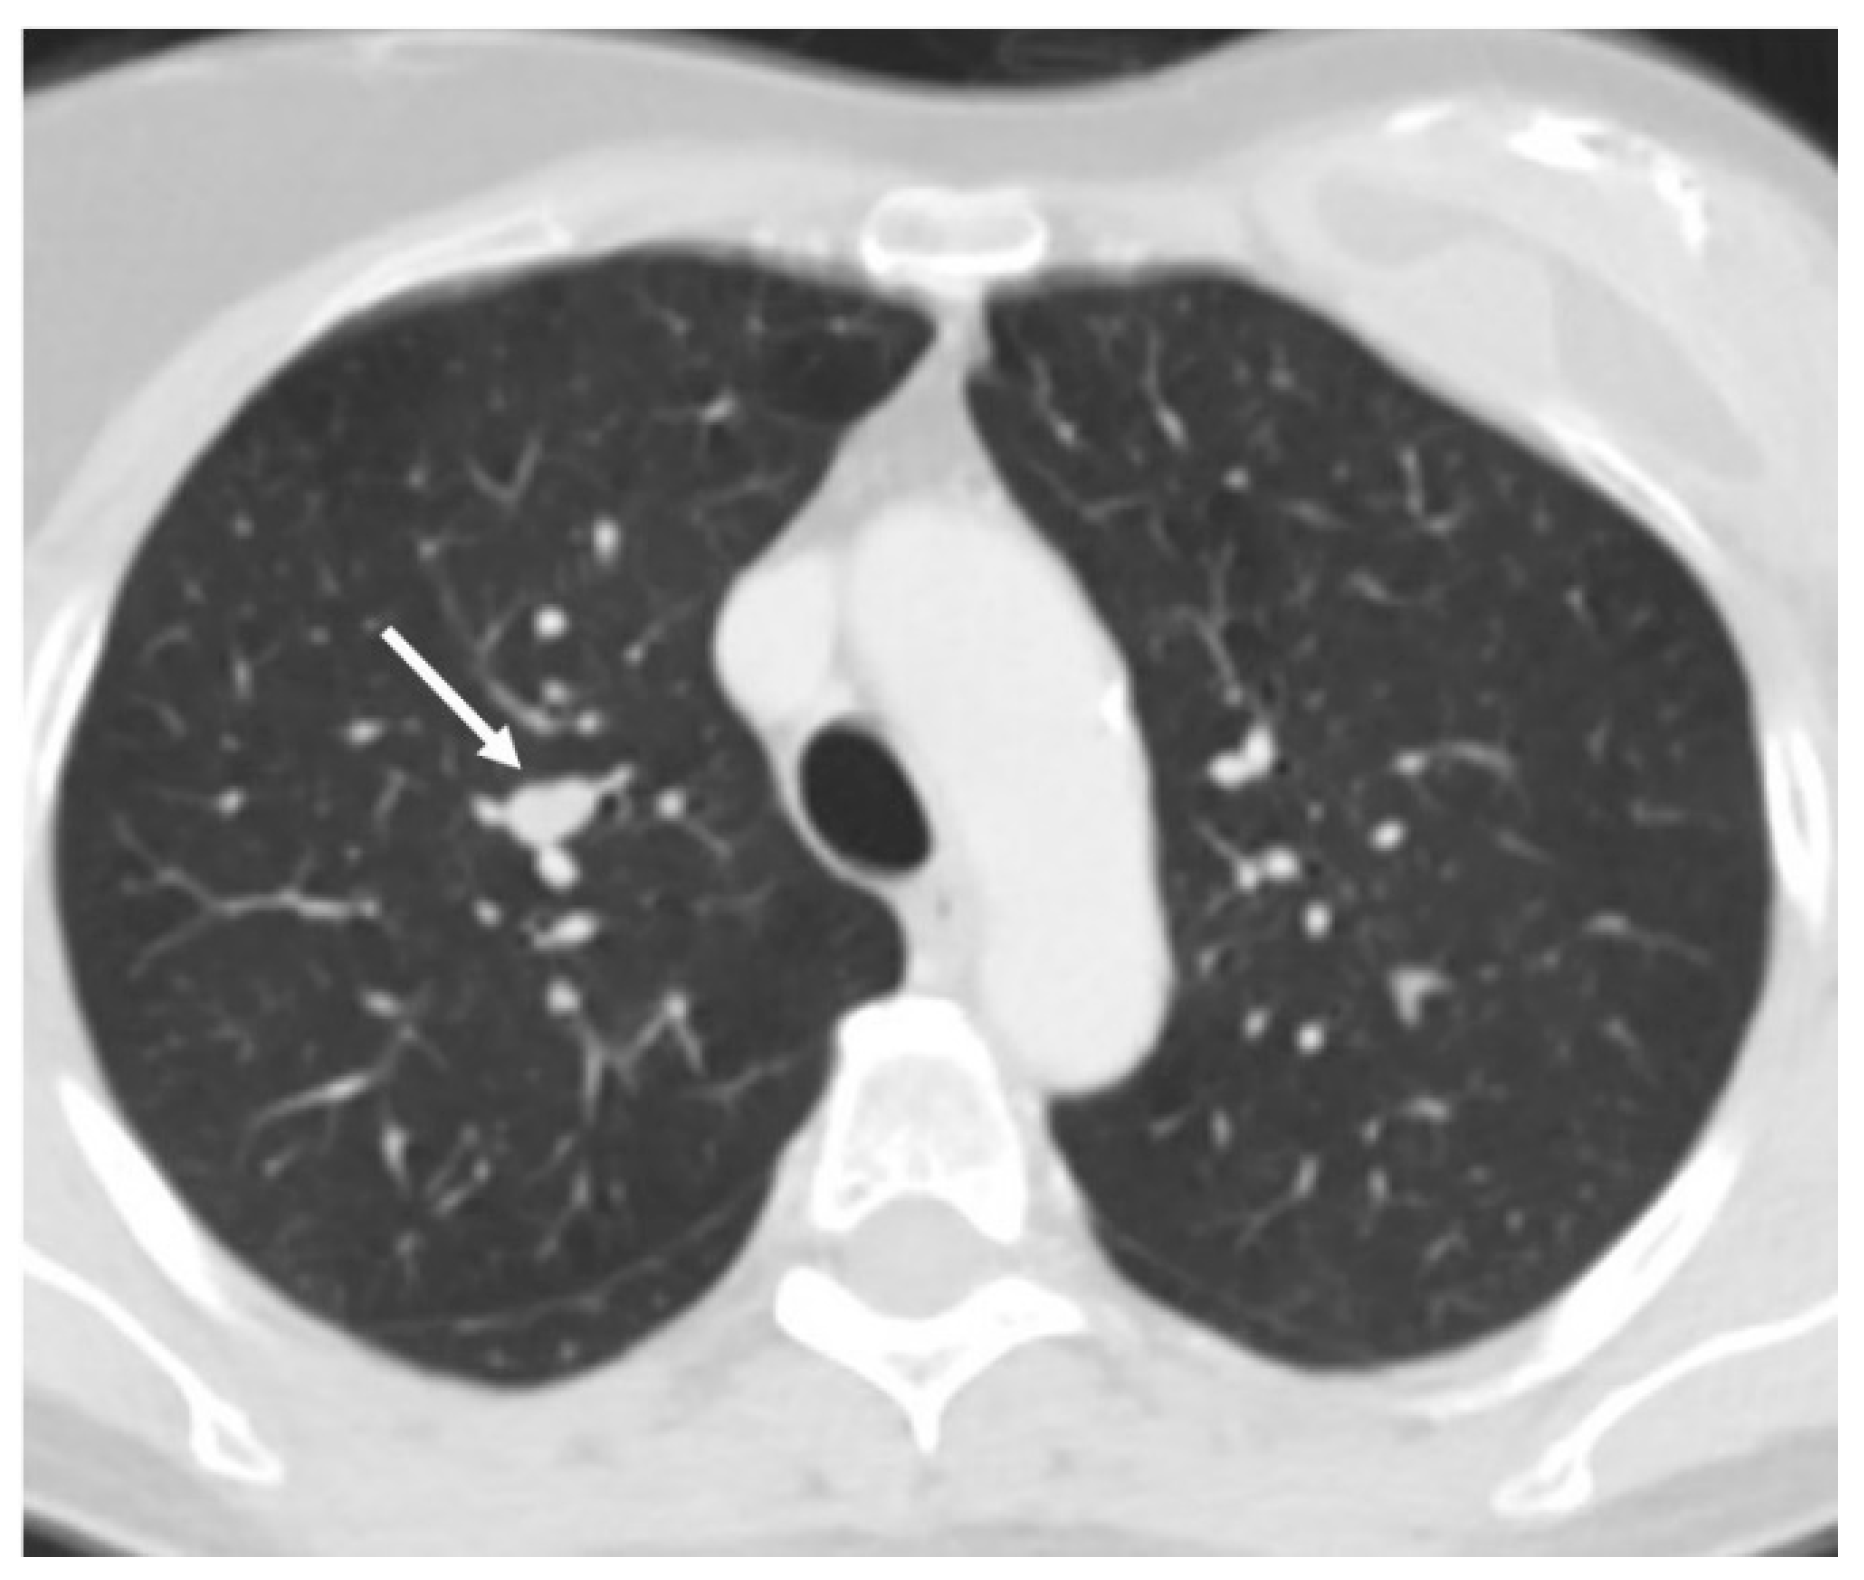

3.2. Radiology

- Meisinger QC, Klein JS, Butnor KJ, Gentchos G, Leavitt BJ. CT features of peripheral pulmonary carcinoid tumors. AJR Am J Roentgenol. 2011 Nov;197(5):1073-80. [CrossRef]

- Baettig E, Molina-Centelles MF, Amr-Rey A, Mancheño-Franch N, Muñoz-Núñez C. Pulmonary neuroendocrine cells: Spectrum of diseases and their radiological-pathological correlations. Radiologia (Engl Ed). 2025 May-Jun;67(3):357-364. [CrossRef]